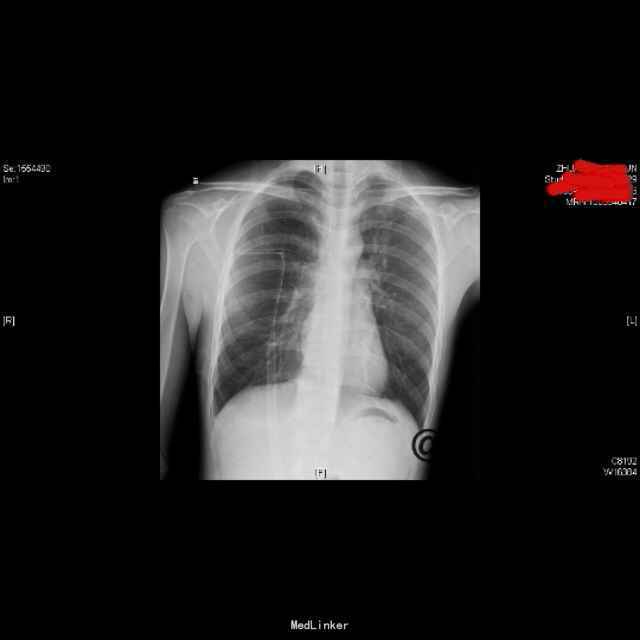

查体:右上肺呼吸音低,余无特殊;心脏、腹部查体未见异常。 辅查: (2015-10-27)行X平片(胸部)检查提示:右侧胸腔引流管置入后改变。 (2015-10-29)胸片:右侧气胸(肺组织压缩约10%),并右侧胸腔引流管置入后改变。 (2015-11-03)行CT(颈胸部CT)检查提示:1、右侧气胸,右侧胸腔积液,右侧胸膜增厚;2、右肺下叶良性硬化性小结节。 (2015-11-09)胸片胸部未见明显异常X线征象。 (2015-10-27)血生化:白介素-69.12ng/L、余无明显异常。 传染病四项、结核感染T细胞检测、大便、小便常规、血常规未见明显异常。 (2015-11-09)复查血常规:嗜酸性粒细胞百分数8.30%、余无明显异常。复查生化:未见明显异常。

诊治经过:患者入院后完善相关检查,排除禁忌后,于10-26行胸腔闭式引流术、置管引流气胸,10-29加负压吸引,11-02予以夹闭引流管24小时,11-03复查胸部CT,阅片示右上肺尖处见少量气体,指示可予拔管处理,继续吸氧。后听诊右上肺呼吸音低,于11-5行床边胸腔抽气术,共抽出900ml气体,予以面罩中流量间断吸氧,11-9复查胸片见右上肺复张。现患者一般情况可,生命体征平稳,经与患者沟通及请示上级医师,给予办理出院。